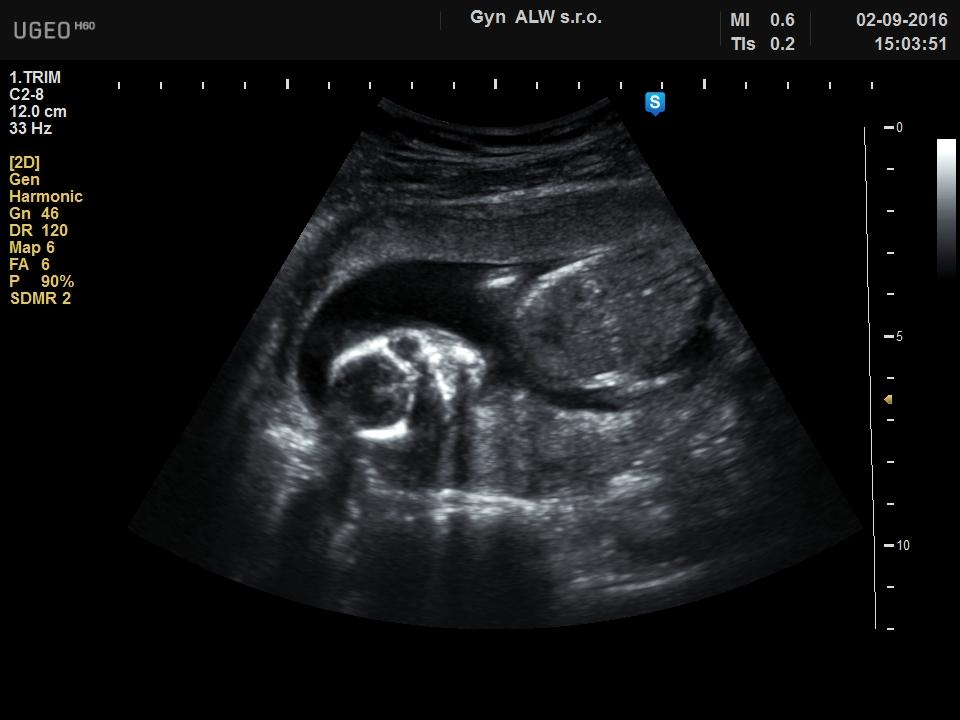

@sss1010 u mě poprvé Terka nechtěla ukázat,co je... Řekli mi to až okolo 28.tt , teď od 13.tt jasný kluk,už od třech doktorů potvrzený a mám v albu i foto a nepochybně je tam 🙂 . Takže za mě to vždy sedělo 🙂! Přeji jen to nej, ať princezny krásně rostou!!!!